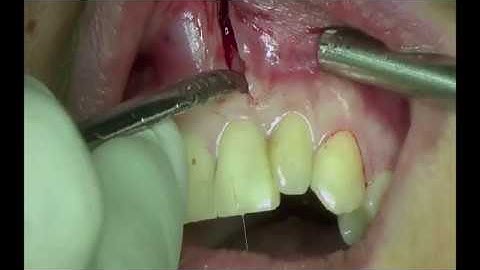

LIVE OPERATION Root Tip Resection with retrograde Filling